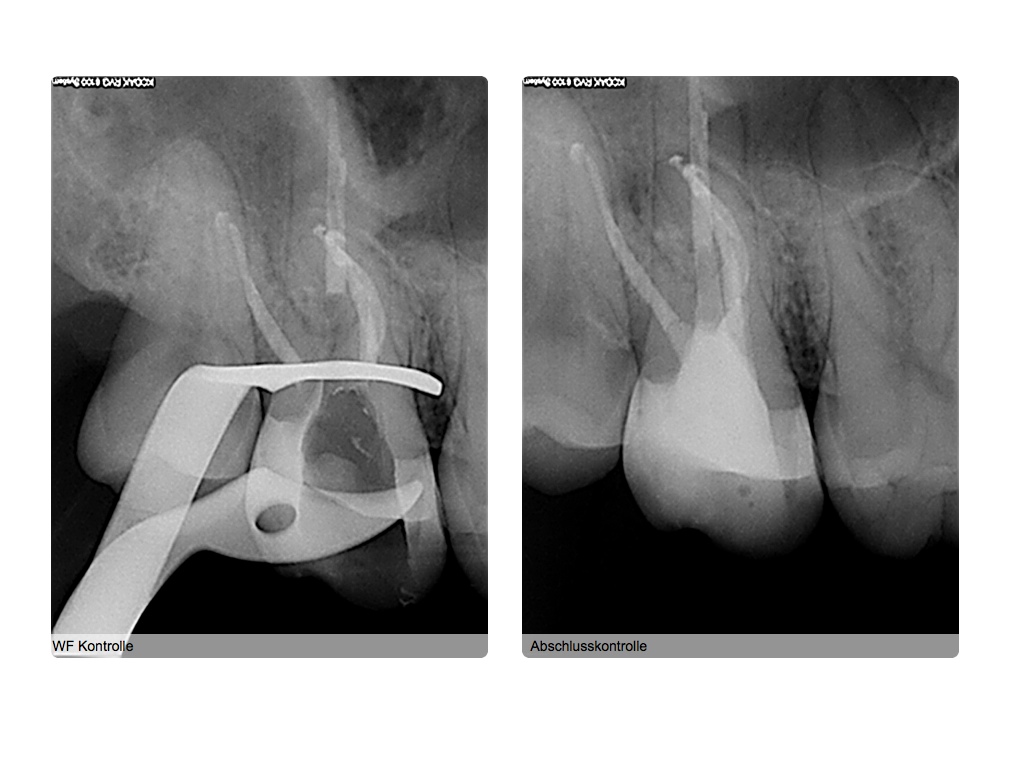

Was würden Sie machen, wenn es Ihr Zahn wäre?